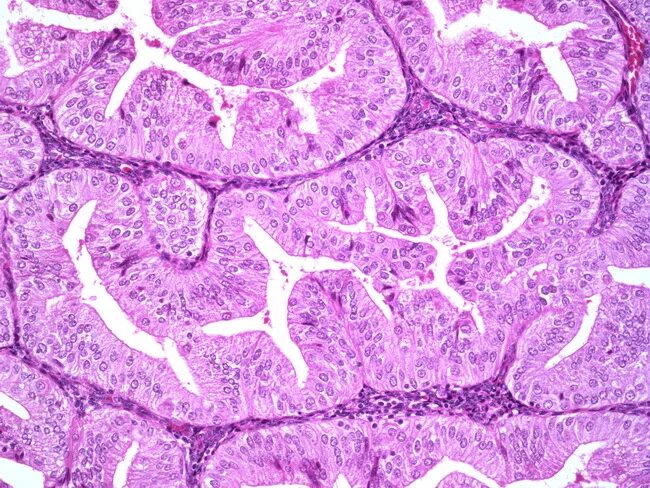

Высокодифференцированная аденокарцинома кишки